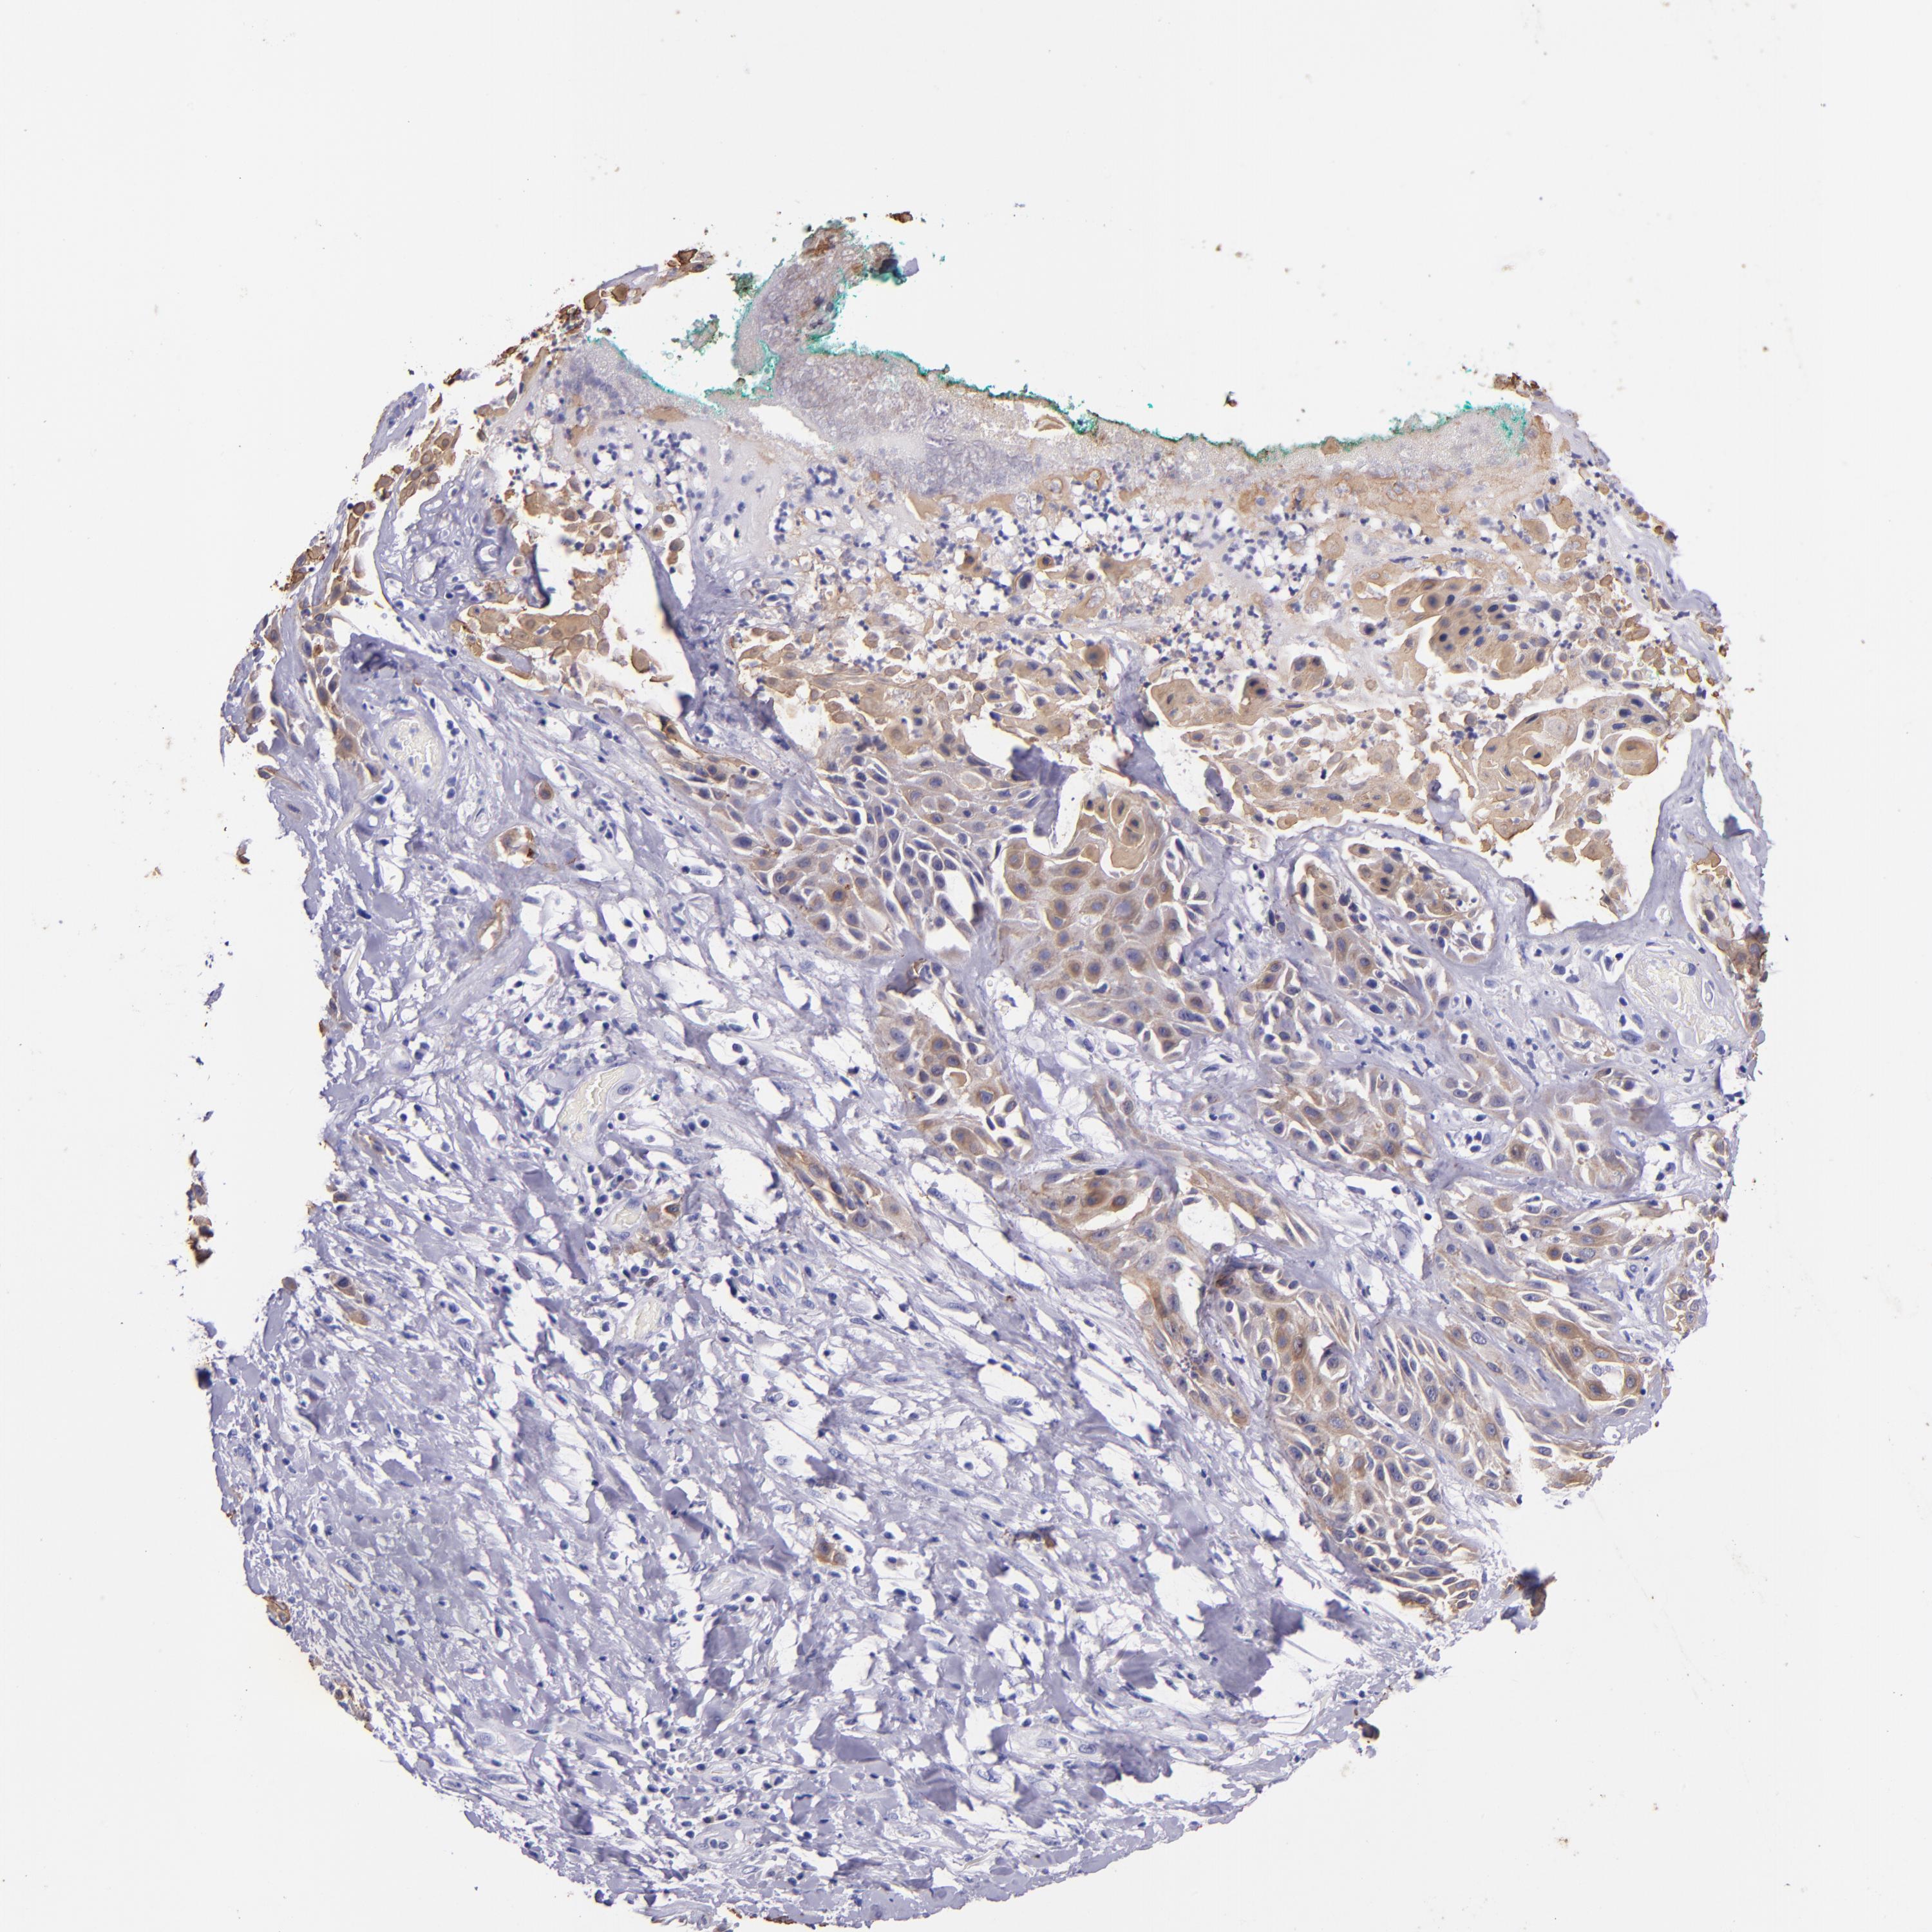

SKIN CANCER - Protein expressioni

A mouse-over function shows sample information and annotation data. Click on an image to view it in a full screen mode. Samples can be filtered based on level of antibody staining by selecting one or several of the following categories: high, medium, low and not detected. The assay and annotation is described here.

Antibody staining in the annotated cell types in the current human tissue is reported as not detected, low, medium, or high, based on conventional immunohistochemistry profiling in selected tissues. This score is based on the combination of the staining intensity and fraction of stained cells.

Each image is clickable and will lead to virtual microscopy that enables deeper exploration of all samples and also displays staining intensity scores, fraction scores and subcellular localization as well as patient and tissue information for each sample.

Antibody HPA034881

Antibody CAB002154

Basal cell carcinoma

Squamous cell carcinoma, NOS